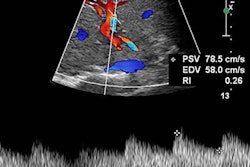

Left: Images of metastatic cervical lymph node. (A) Irregular low-echo nodules can be seen on conventional ultrasound, but the structure of the lymph node hilum is unclear. (B) Using "quality mode" on the VTIQ software, the lesion appears green with some yellow, showing good elasticity. (C) Using "velocity mode" on the VTIQ software, the shear-wave velocity values are shown for different points in the lesion. Right: Images of nonmetastatic lymph node. (A) An oval hypoechoic nodule can be seen on the conventional ultrasound, but the structure of the lymph node hilum is also unclear. (B) and (C), same descriptions as for previous image. All images courtesy of the Journal of Ultrasound in Medicine.False negatives